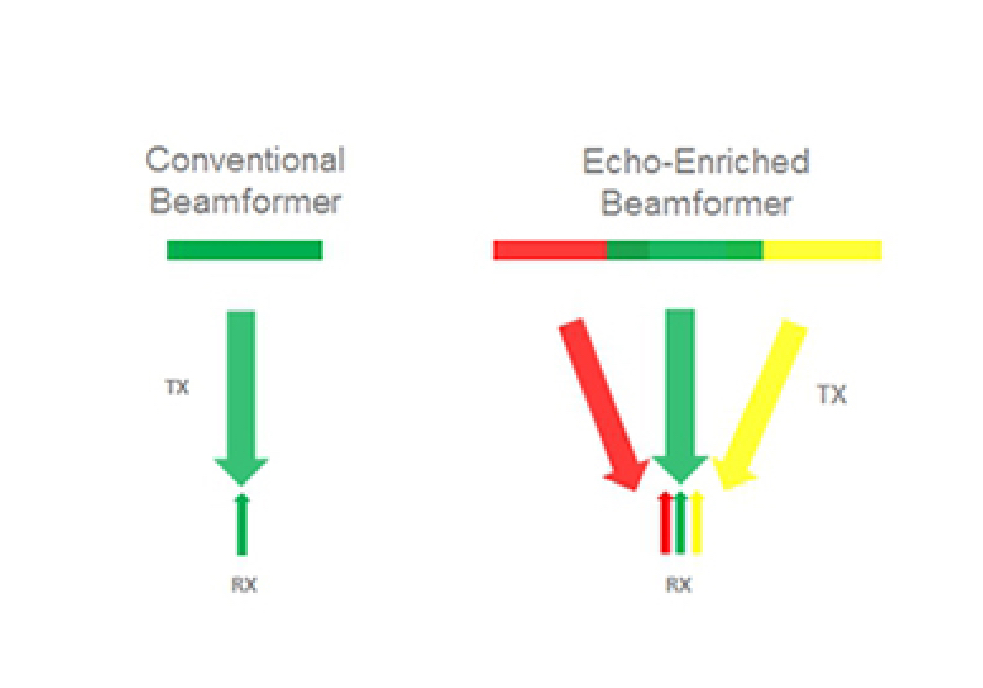

Echo-enriched Beam Forming

Echo-enriched beam former permits the use of traditionally neglected echo signals of adjacent beams to form one finer and stronger imaging beam, providing better ŌĆśout-of-focusŌĆÖ image resolution and deeper image penetration.